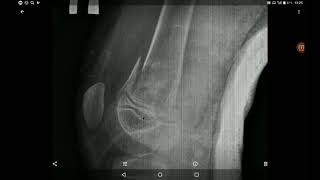

Перелом бедра. Закрытая репозиция. Рентген анатомия. Рентген диагностика.

медицинаонлайн #хирургия #операция #изнанкахирургии#перелом#рентген #бедро Благодарю за просмотр. Ставьте лайки, обязательно ...